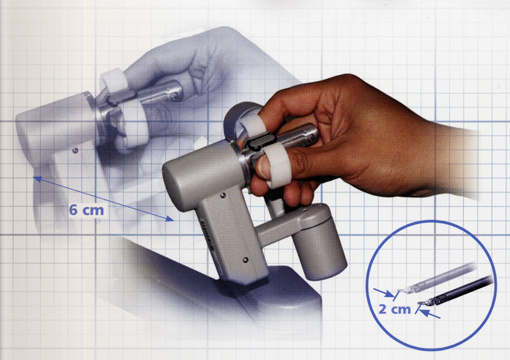

Τα λεπτά πολυ-αρθρωτά εργαλεία του συστήματος da Vinci, που μοιάζουν σαν μικρά ανθρώπινα χεράκια, έχουν πολύ μεγαλύτερο εύρος κινήσεων απ’ ότι ο ανθρώπινος καρπός. Το ρομποτικό σύστημα da Vinci φιλτράρει άμεσα κάθε τρέμουλο των χεριών του χειρουργού και κάνει τις κινήσεις πιο πλαστικές και κλιμακωτές δίνοντας περισσότερη βαρύτητα στην ακρίβεια και και στην φυσική ροή της κίνησης των ρομποτικών εργαλείων.

Τα ρομποτικά εργαλεία του συστήματος da Vinci έχουν την διάμετρο ενός μολυβιού.

Οι κινήσεις των ρομποτικών εργαλείων είναι διαισθητικές (κίνηση προς τ’ αριστερά του χειριστηρίου μετακινεί το ρομποτικό εργαλείο επίσης προς τ’ αριστερά) και κλιμακωτές (κίνηση 6 εκταοστών του χειριστηρίου συνεπάγεται κίνηση 2 εκατοστών του ρομποτικού εργαλείου προς την ίδια φορά)